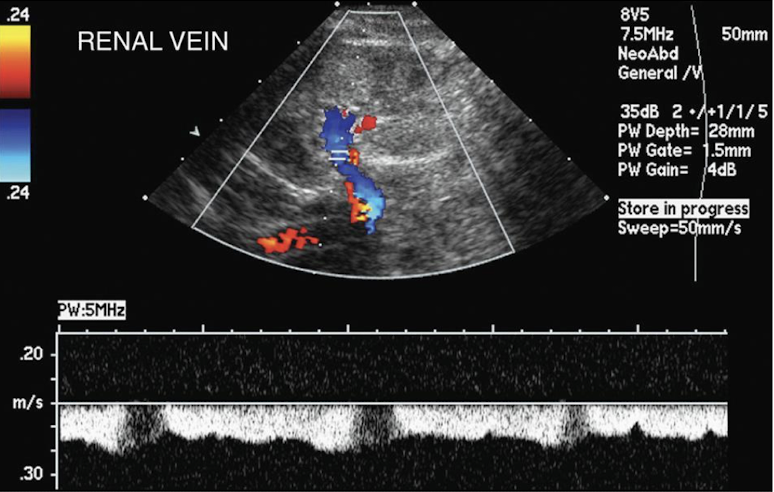

renal vein Doppler waveform

spontaneous and variable (similar to IVC)